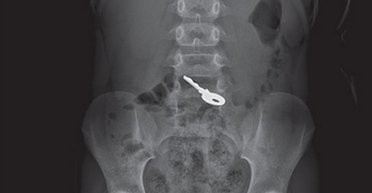

Мать обратилась к врачам только на следующий день после инцидента. Несмотря на отсутствие симптомов, рентген выявил ключ в желудке ребенка. Через 72 часа предмет вышел естественным путем.